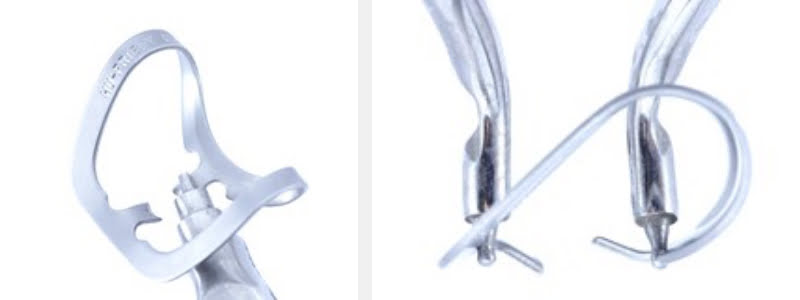

Modifying a 212 Clamp

Utilizing absolute isolation with a rubber dam aided by a modified 212 clamp with one of its arches cut to decrease the force it exerts over the tooth will help reduce the risk of tooth fracture caused by a clamp, decreasing trauma to the periodontal tissue. In 1961, these advantages were described by Ingraham and Rex for the Gold Foil Technique.

To facilitate the use of a previously cut 212 modified clamp on the anterior and posterior teeth, a modification is made by making an internal bevel on the lingual surface of the clamp jaw.

When used on molars, the bevel increases the clamp’s stability, enhancing the clamp adjustment on the treated tooth’s cervical vestibular and lingual surface. This will turn the modified 212 clamp into a “universal clamp” that can be used in various clinical situations on anterior, posterior, upper, or lower teeth.

After making the bevel, a heat treatment is done on both clamp jaws and their position is changed to achieve a proper and better adjustment on the tooth surface that has root exposure. The vestibular jaw of the clamp will be tilted with a cervical inclination and the lingual jaw will be tilted with a coronal inclination — this way damage to the gum will be reduced.

These modifications will optimize tissue retraction during restorative procedures. The most significant distance obtained between the clamp jaws after the modification and the remaining arch will provide the clinician with the proper working space for an adequate composite resin stratification and proper finishing and polishing of the restoration.